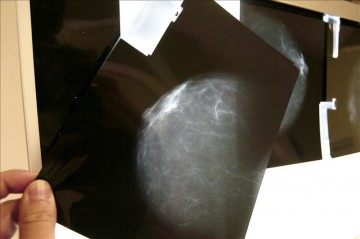

Madrid, 2 sep (EFE).- Un proyecto de investigación español ha demostrado, por primera vez, que el consumo de alimentos propios de la dieta mediterránea puede reducir el riesgo de desarrollar un cáncer de mama hasta en un 30 por ciento.

Madrid, 2 sep (EFE).- Un proyecto de investigación español ha demostrado, por primera vez, que el consumo de alimentos propios de la dieta mediterránea puede reducir el riesgo de desarrollar un cáncer de mama hasta en un 30 por ciento.

El cáncer de mama es uno de los tumores más frecuentes en las mujeres españolas y cada año se diagnostican aproximadamente 26.000 casos nuevos, el 30 por ciento de todos los cánceres detectados en mujeres en España.